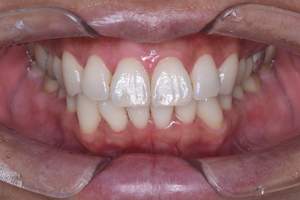

歯石除去

治療前

治療後

| 年齢 | 40歳・男性 |

| 主訴 | 歯石をとりたい |

| 治療内容 | 歯石除去 |

| 治療期間 | 30分 |

| 費用 | 約2,000円 |

| リスク・副作用 | ・歯ぐきの炎症が強いと歯石を取る際に出血することがあります。 ・処置後に歯がしみることがあります。 ・歯と歯の間に隙間ができるので、息が漏れ発音しにくいと感じることがあります。 ・歯ぐきの炎症が軽減すると歯ぐきが引き締まり、歯が長く見えることがあります。 |